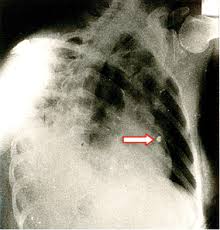

Los peritos de la Policía Científica, certificaron que el cuerpo presentaba como mínimo, un certero impacto de bala en el tórax.